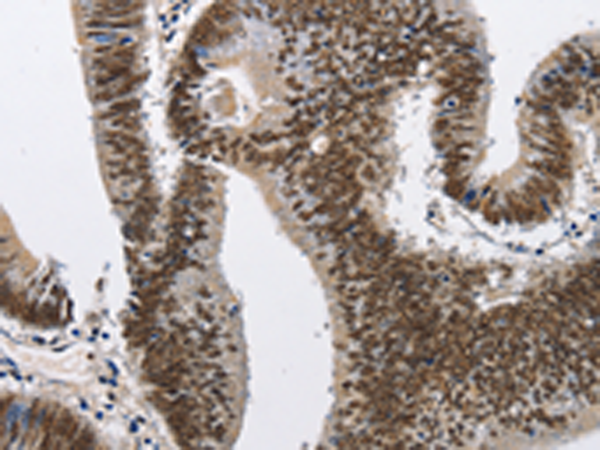

IHC positive control: |

Human colon cancer and human esophagus cancer |